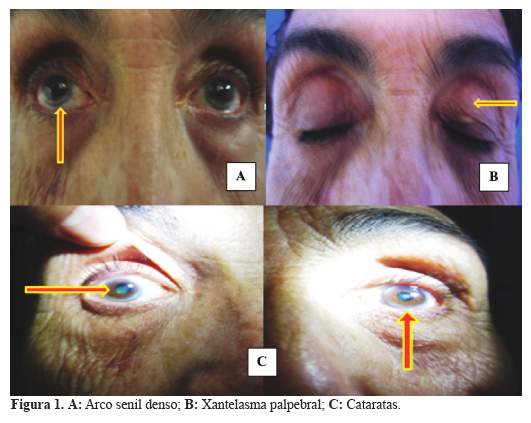

El examen clínico y por sistemas: mostró a una paciente con funciones vitales normales. En la facies destacaba presencia de arco blanquecino denso bilateral y de xantelasma en el párpado superior izquierdo, así como opacidad en ambos cristalinos, por exploración oftalmológica (figura 1 (A,B,C)). La exploración de los pares craneales normales en su totalidad, que incluyó el fondo del ojo, sin alteraciones.

Los xantomas tendinosos aquilianos, biopsiados mostraron la naturaleza de la enfermedad, al igual que la presencia del arco senil tempranamente aparecidos, antes de los 30 años, las cataratas, la presencia de xantoma en el cuerno ventricular derecho por la especialidad y la osteoporosis estarían indicando un estado avanzado de la enfermedad por XCT. El estudio con resonancia magnética del cerebro (RM), puso en evidencia los cambios morfológicos del tejido cerebral, asi como , la penetrancia del colagenol en estructuras específicas empleando la incidencia del FLAIR.

La presencia de los hallazgos oftalmológicos y las características morfológicas de las regiones aquilianas permitieron sospechar clínicamente de la la presencia de xantomatosis que se confirmó mediante los resultados histopatológicos de la biopsia efectuada. Los resultados de la exploración neurológica mostraron un estado demencial severo asociado a definidas alteraciones de la función cerebelosa.